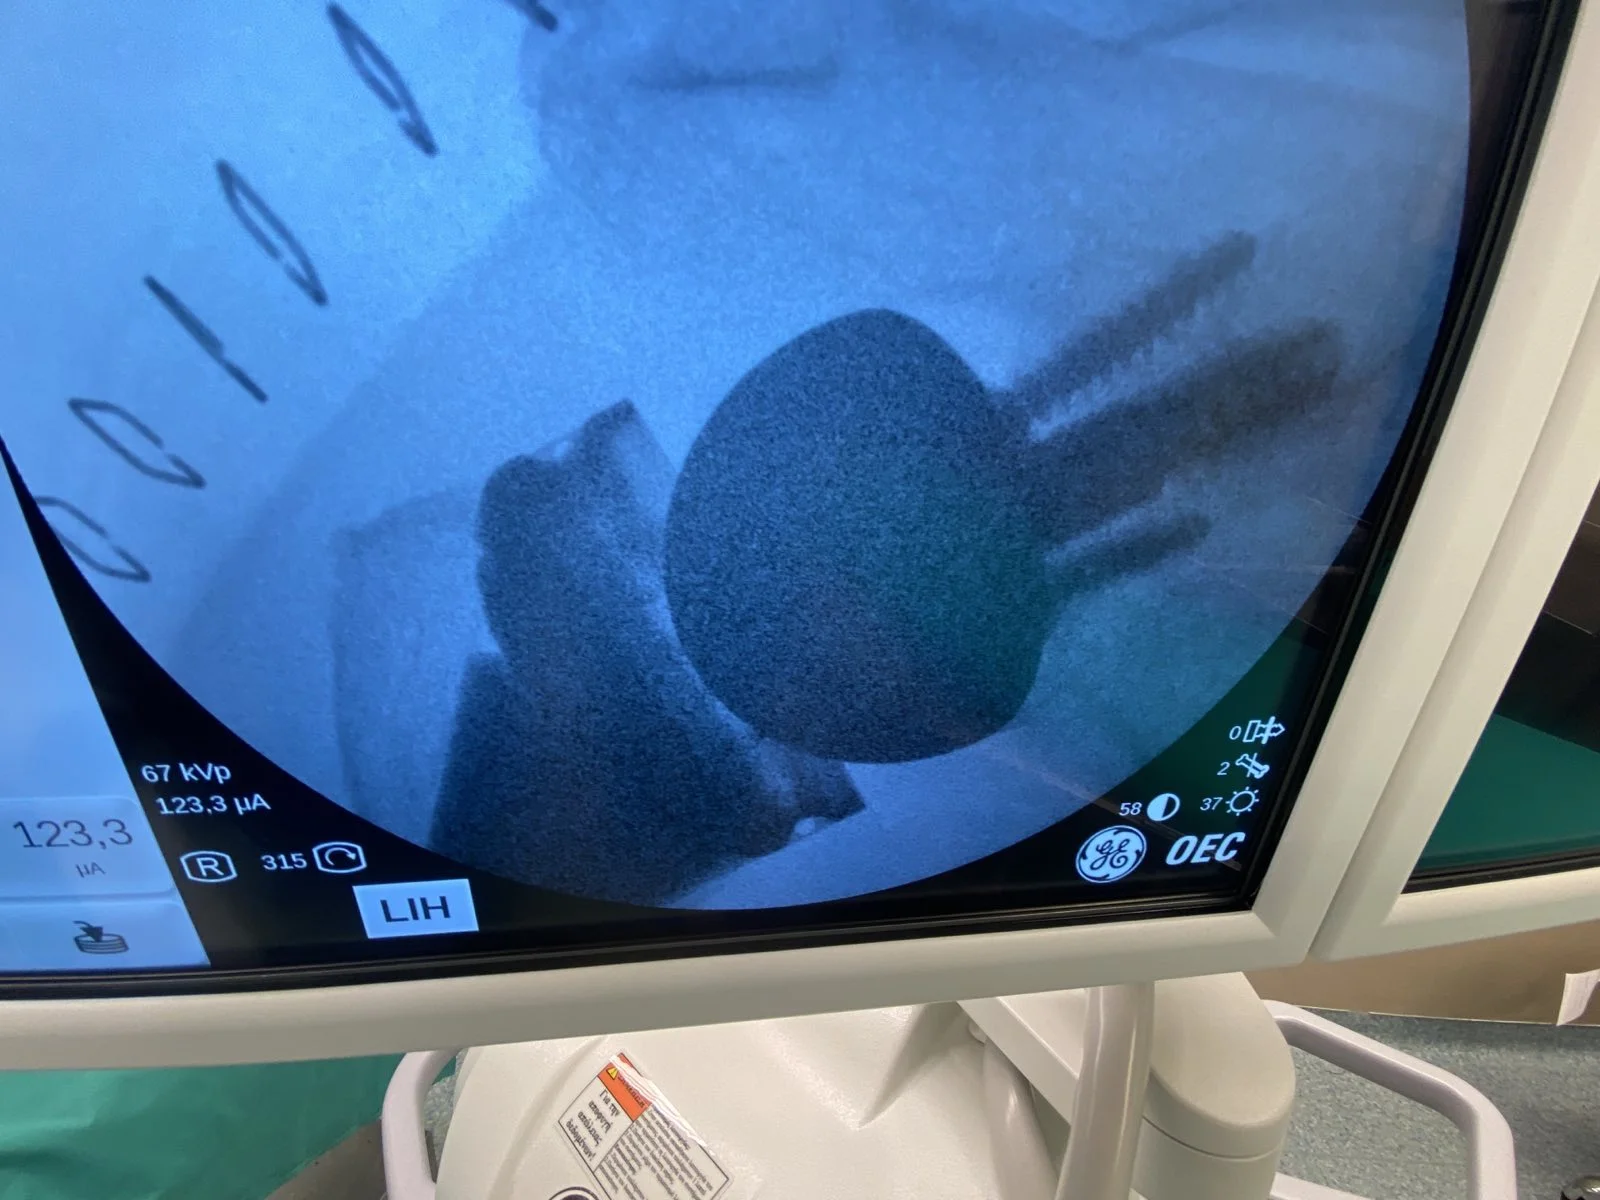

Με μεγάλη χαρά σας ανακοινώνουμε τη πρώτη εμφύτευση στην Ελλάδα της Ολικής Ανάστροφης Αρθροπλαστικής ώμου τύπου Univers Reverse with MGS glenoid της εταιρίας Arthrex μια δοκιμασμένη και εξαιρετική αρθροπλαστική με μακροχρόνια και άριστη βιωσιμότητα στα καλύτερα κέντρα της Αμερικής, ταυτόχρονα ευέλικτη και εξατομικευμένη στην ανατομία και στις ανάγκες του κάθε ασθενή.

Η πρόθεση μιμείται την κανονική ανατομία καθώς το κόψιμο γίνεται στις 135 μοίρες και ανάλογα με τον κάθε ασθενή και η πρόθεση της ωμογλήνης πέρα από το τελευταίο σχεδιασμό και τα καλύτερα υλικά, σταθεροποιείται από μια πανίσχυρη κεντρική βίδα και έχει μηχανισμούς με τους οποίους ο χειρουργός έχει την δυνατότητα και κλειδώνει το κάθε μέρος της πρόθεσης ώστε να έχει ένα αξιόπιστο άριστο αποτέλεσμα κάθε φορά.